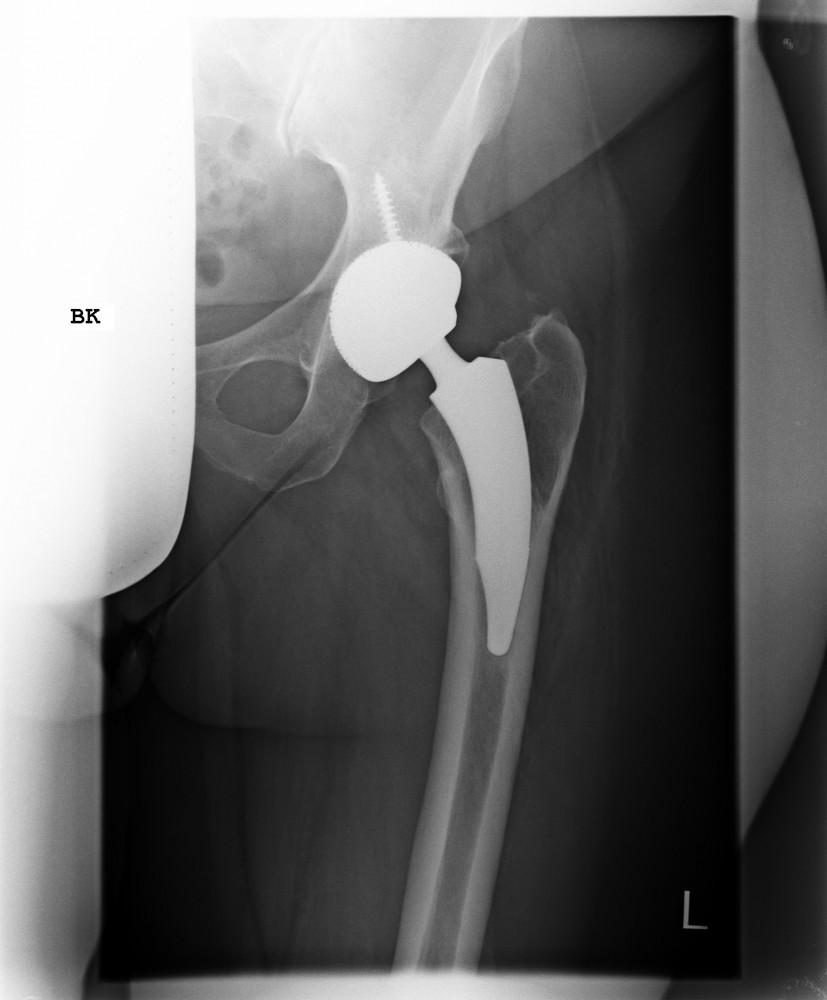

Das künstliche Hüftgelenk besteht aus vier Komponenten. Im Becken erfolgt die Implantation einer Pfannenkomponente, meist zementfrei, als Pressfit- oder Schraubimplantat. In dieser Titanpfanne wird ein sogenanntes Inlay aus hochverdichtetem Kunststoff verklemmt.

Im Bereich des Oberschenkels wird eine Schaftkomponente zementfrei (aus Titan) oder zementiert (aus einer Kobalt/Chrom Legierung) implantiert. Am oberen Ende befindet sich ein sogenannter Steckkonus auf den der künstliche Hüftkopf (Metall/Keramik/Oxinium) aufgebracht wird. Eine Komponente wird dann zementiert, wenn eine erheblich geminderte Knochendichte oder Osteoporose vorliegt.